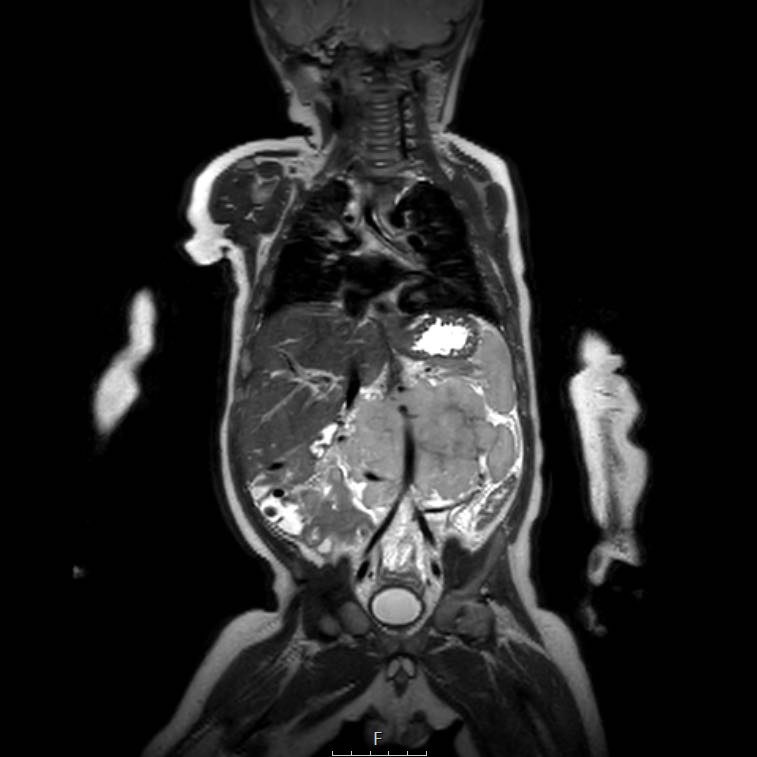

Cuộn qua chuỗi ảnh T2 theo mặt phẳng coronal.

Nghiên cứu các hình ảnh và sau đó tiếp tục đọc.

The findings are:

- Mass with encasement of the aorta and splanchnic vessels.

- Lan rộng dọc theo cột sống ngực nhưng không xâm lấn vào ống sống.

- Small liver metastases.

- Left supraclavicular mass.

Mức độ lan rộng của khối u được đánh giá rõ ràng trên chuỗi xung TSE T2 weighted 3D theo mặt phẳng axial.

The left kidney is compressed and displaced caudally.

Có di căn hạch bạch huyết cạnh động mạch chủ (mũi tên vàng nhỏ).

Nguyên ủy của thân tạng và động mạch mạc treo tràng trên bị khối u bao quanh (đầu mũi tên).

Tĩnh mạch chủ dưới bị đẩy ra phía trước (mũi tên xanh).

Xẹp phổi hai bên ở vùng lưng thường được thấy trên MRI, vì việc kiểm tra được thực hiện dưới gây mê.